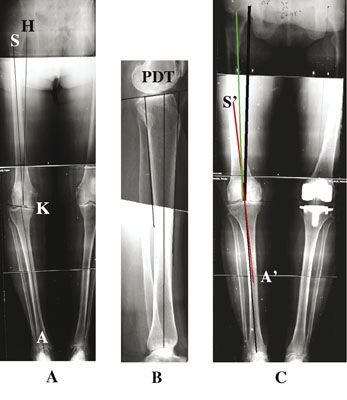

Mise au point Dégradations rotatoires des genu varum , Marc Raguet Polyclinique Priollet Courlancy, 51000 Châlons en Champagne, France 🖂 marc.raguet@wanadoo.fr , le groupe ARTRO Clinique d’Argonay-Annecy, 74370 Annecy, France N°173 - Avril 2008 ● 36 min de lecture